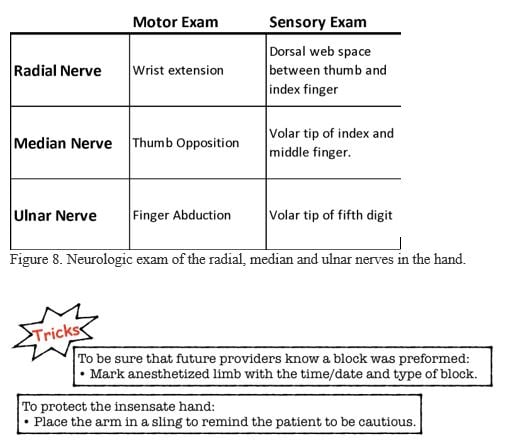

- Neurovascular exam before and after procedure (Figure 8)

- After the procedure the neurologic exam should be repeated when the block wears off to document return of function.